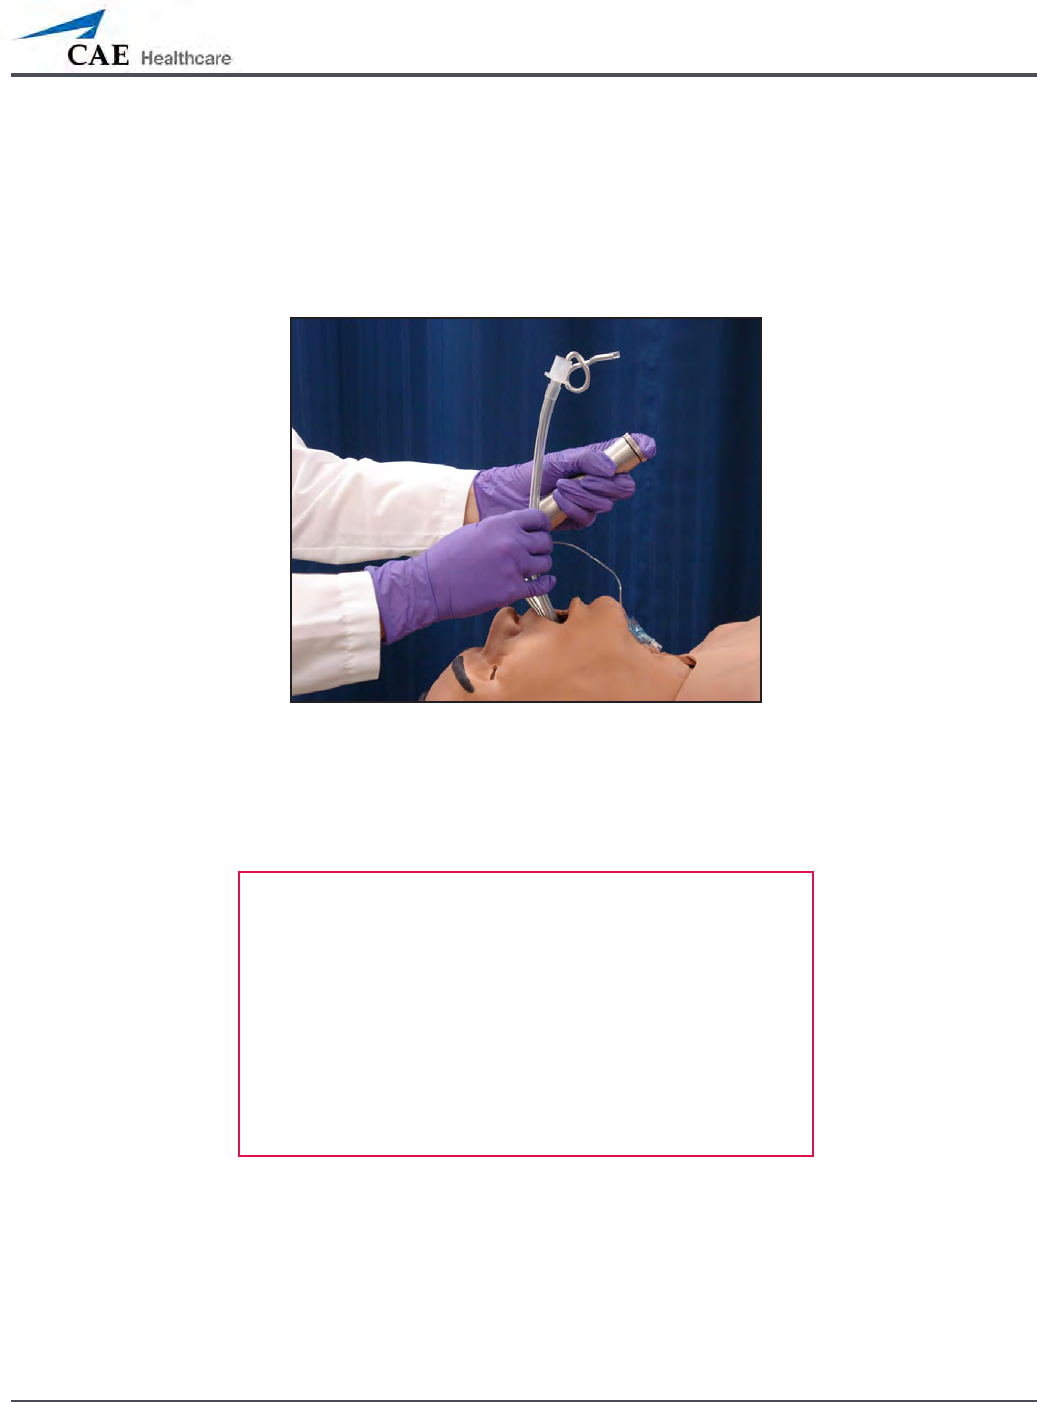

Realistic Upper Airway (Prehospital Only)

The upper airway of METIman Prehospital is designed to allow for intubation and

laryngoscopy. Oral and nasal intubation can be performed using a variety of airway devices,

including LMAs (3), endotracheal tubes (6.5 mm to 7.5 mm), nasal-pharyngeal airways (30 mm)

and oropharyngeal airways (90 mm).

Intubation

The simulator detects and responds appropriately to right mainstem intubation, and an event

is recorded in the Event Log.

Intubation incorrectly applied into the esophagus causes abdominal distension.

IMPORTANT

Airways can be damaged by improper insertion of an

airway adjunct (e.g. endotracheal tube). To protect the

airway, lubricate the adjunct prior to insertion using the

silicone spray provided.

Use ONLY the provided SILICONE SPRAY to lubricate the

adjunct. NEVER use a water-based lubricant because of

resulting residue damage.